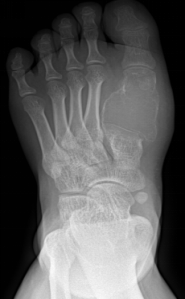

先天性马蹄内翻足

手足短骨解剖及常见疾病的影像学表现